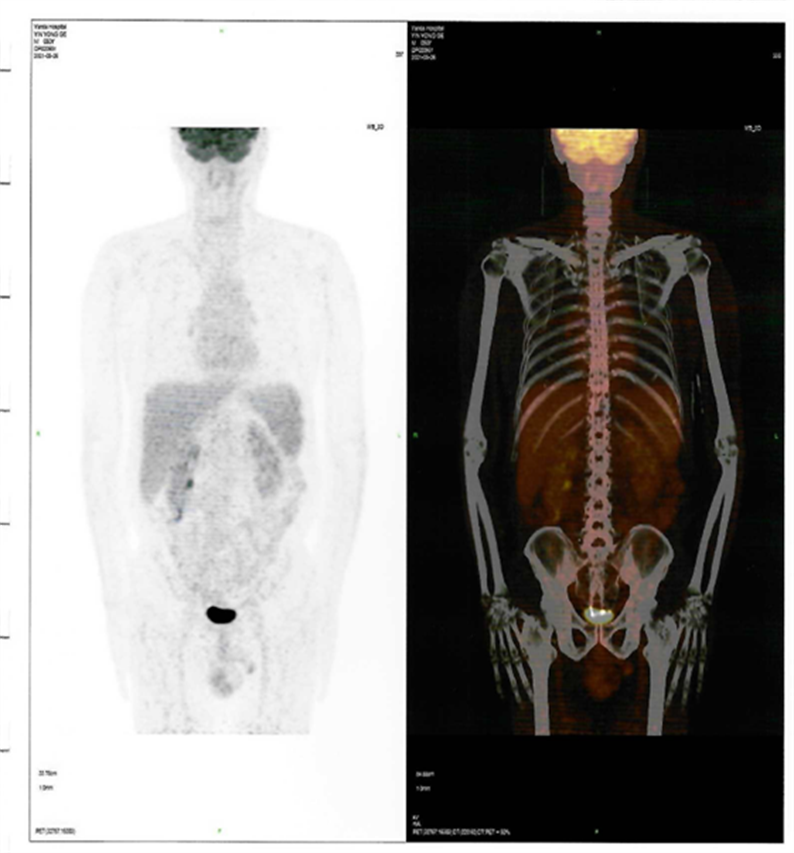

近日,燕達陸道培醫(yī)院血液科二病區(qū)傳來好消息,一位罹患T細胞淋巴瘤前期在美國治療復(fù)發(fā)的患者,428日,在我院回輸CD7 CAR-T細胞,526日經(jīng)PET-CT檢查,顯示CR(完全緩解)。

CAR-T治療后30

回輸后一度出現(xiàn)了一級CRS反應(yīng),癥狀可控,526日,回輸后+28天復(fù)查PET-CT顯示CR(完全緩解)。預(yù)祝黃山先生接下來的治療一切順利!